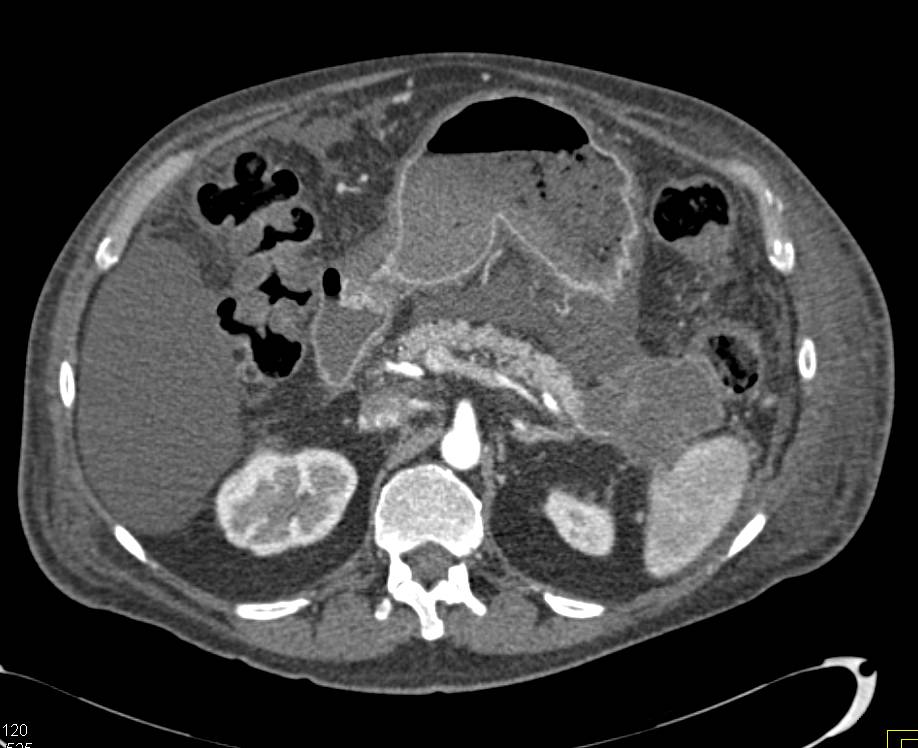

Subtle Adenocarcinoma of the Head of the Pancreas